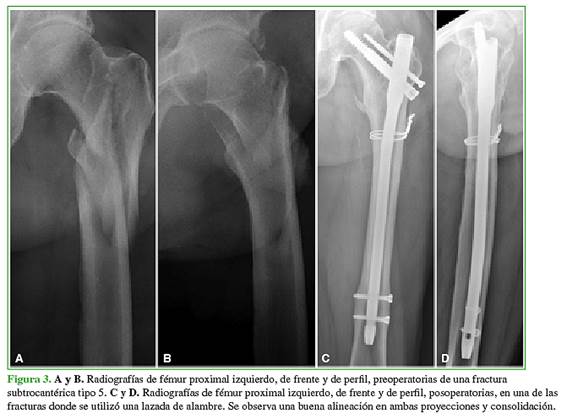

La reducción se clasificó como buena en 53 (91,4%) casos, aceptable en tres (5,2%) y regular en dos (3,4%) (Figura 3).

Cinco (8,6%) pacientes, todos del grupo tratado sin lazadas, presentaron desejes: uno solo en la proyección anteroposterior (12º); uno en las proyecciones anteroposterior y lateral (12º y 10º, respectivamente) y dos solo en la proyección lateral (10°-15°). El restante presentó un defecto rotatorio de 15°. La distancia punta-ápice de la serie fue de 15,41 ± 3,74 mm.